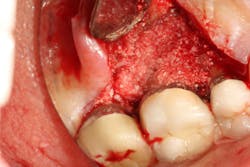

Another advancement in the field of periodontal regenerative medicine has been due to the use of growth factors, proteins, and stem cells. The ability to repair/regenerate a diseased tooth is often dependent upon the extent of the defect, namely the number of bone walls that are left surrounding the tooth. The more bone walls a tooth has left around it (maximum of four), the more blood supply, containment, and space maintenance your graft material will have (figure 5). Bone defects that have three to four walls missing are the hardest to repair and may be slated for extraction (figure 6). By adding growth-stimulating factors to your regular bone grafts (figure 7), an increase in osteopromotive potential occurs that can have the ability to overcome a deficiency of bone walls. (15) Simply stated, your bone graft can become alive, and teeth that were once unable to be repaired now have a chance.

Figure 7: Same tooth undergoing periodontal regeneration surgery with anorganic bovine bone (Bio-Oss Collagen, Geistlich Biomaterials) and platelet-derived growth factor (PDGF)